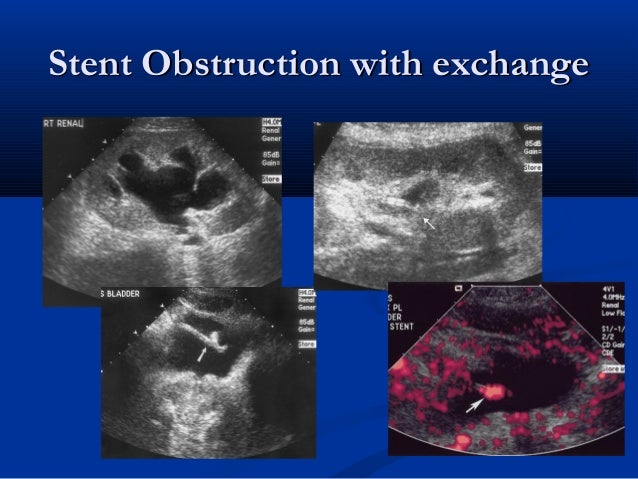

- Ureteral stent obstruction icd 10